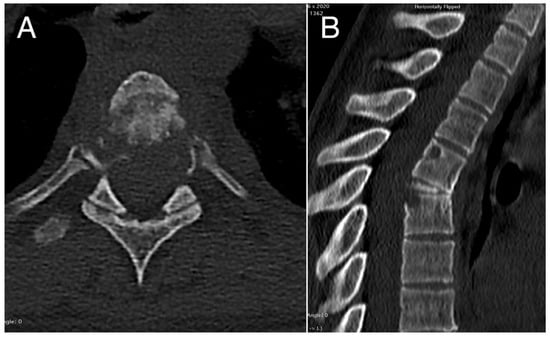

Figure 2. Pre-operative axial (A) and sagittal (B) CT scans showing the pathological collapse of T5 vertebral body with osteolysis affecting also the corresponding pedicle regions, the adjacent upper portion of T6 vertebral body, and the posterior-upper angle of the T4 vertebral body.